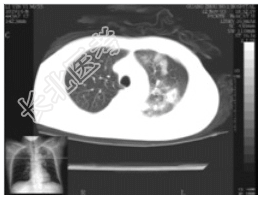

- [材料题] 女性,55岁,10余天前出现午后潮热(约38.5℃),无伴盗汗,有咳,痰少、带血丝,发病以来体重减轻5Kg,大小便正常,否认肺结核等病史。一般情况:无特殊。体查:左胸呼吸运动减弱,左侧语颤增强,左上肺叩诊浊音,并闻及干性啰音,语音传导增强。实验室检查:血常规及肿瘤五项、AFP、CEA均在正常范围。痰涂片未见真菌,未见抗酸杆菌,发现少量酵母样菌。

- 简答题1、患者的诊断及依据是什么?

- 简答题2、鉴别诊断有哪些?